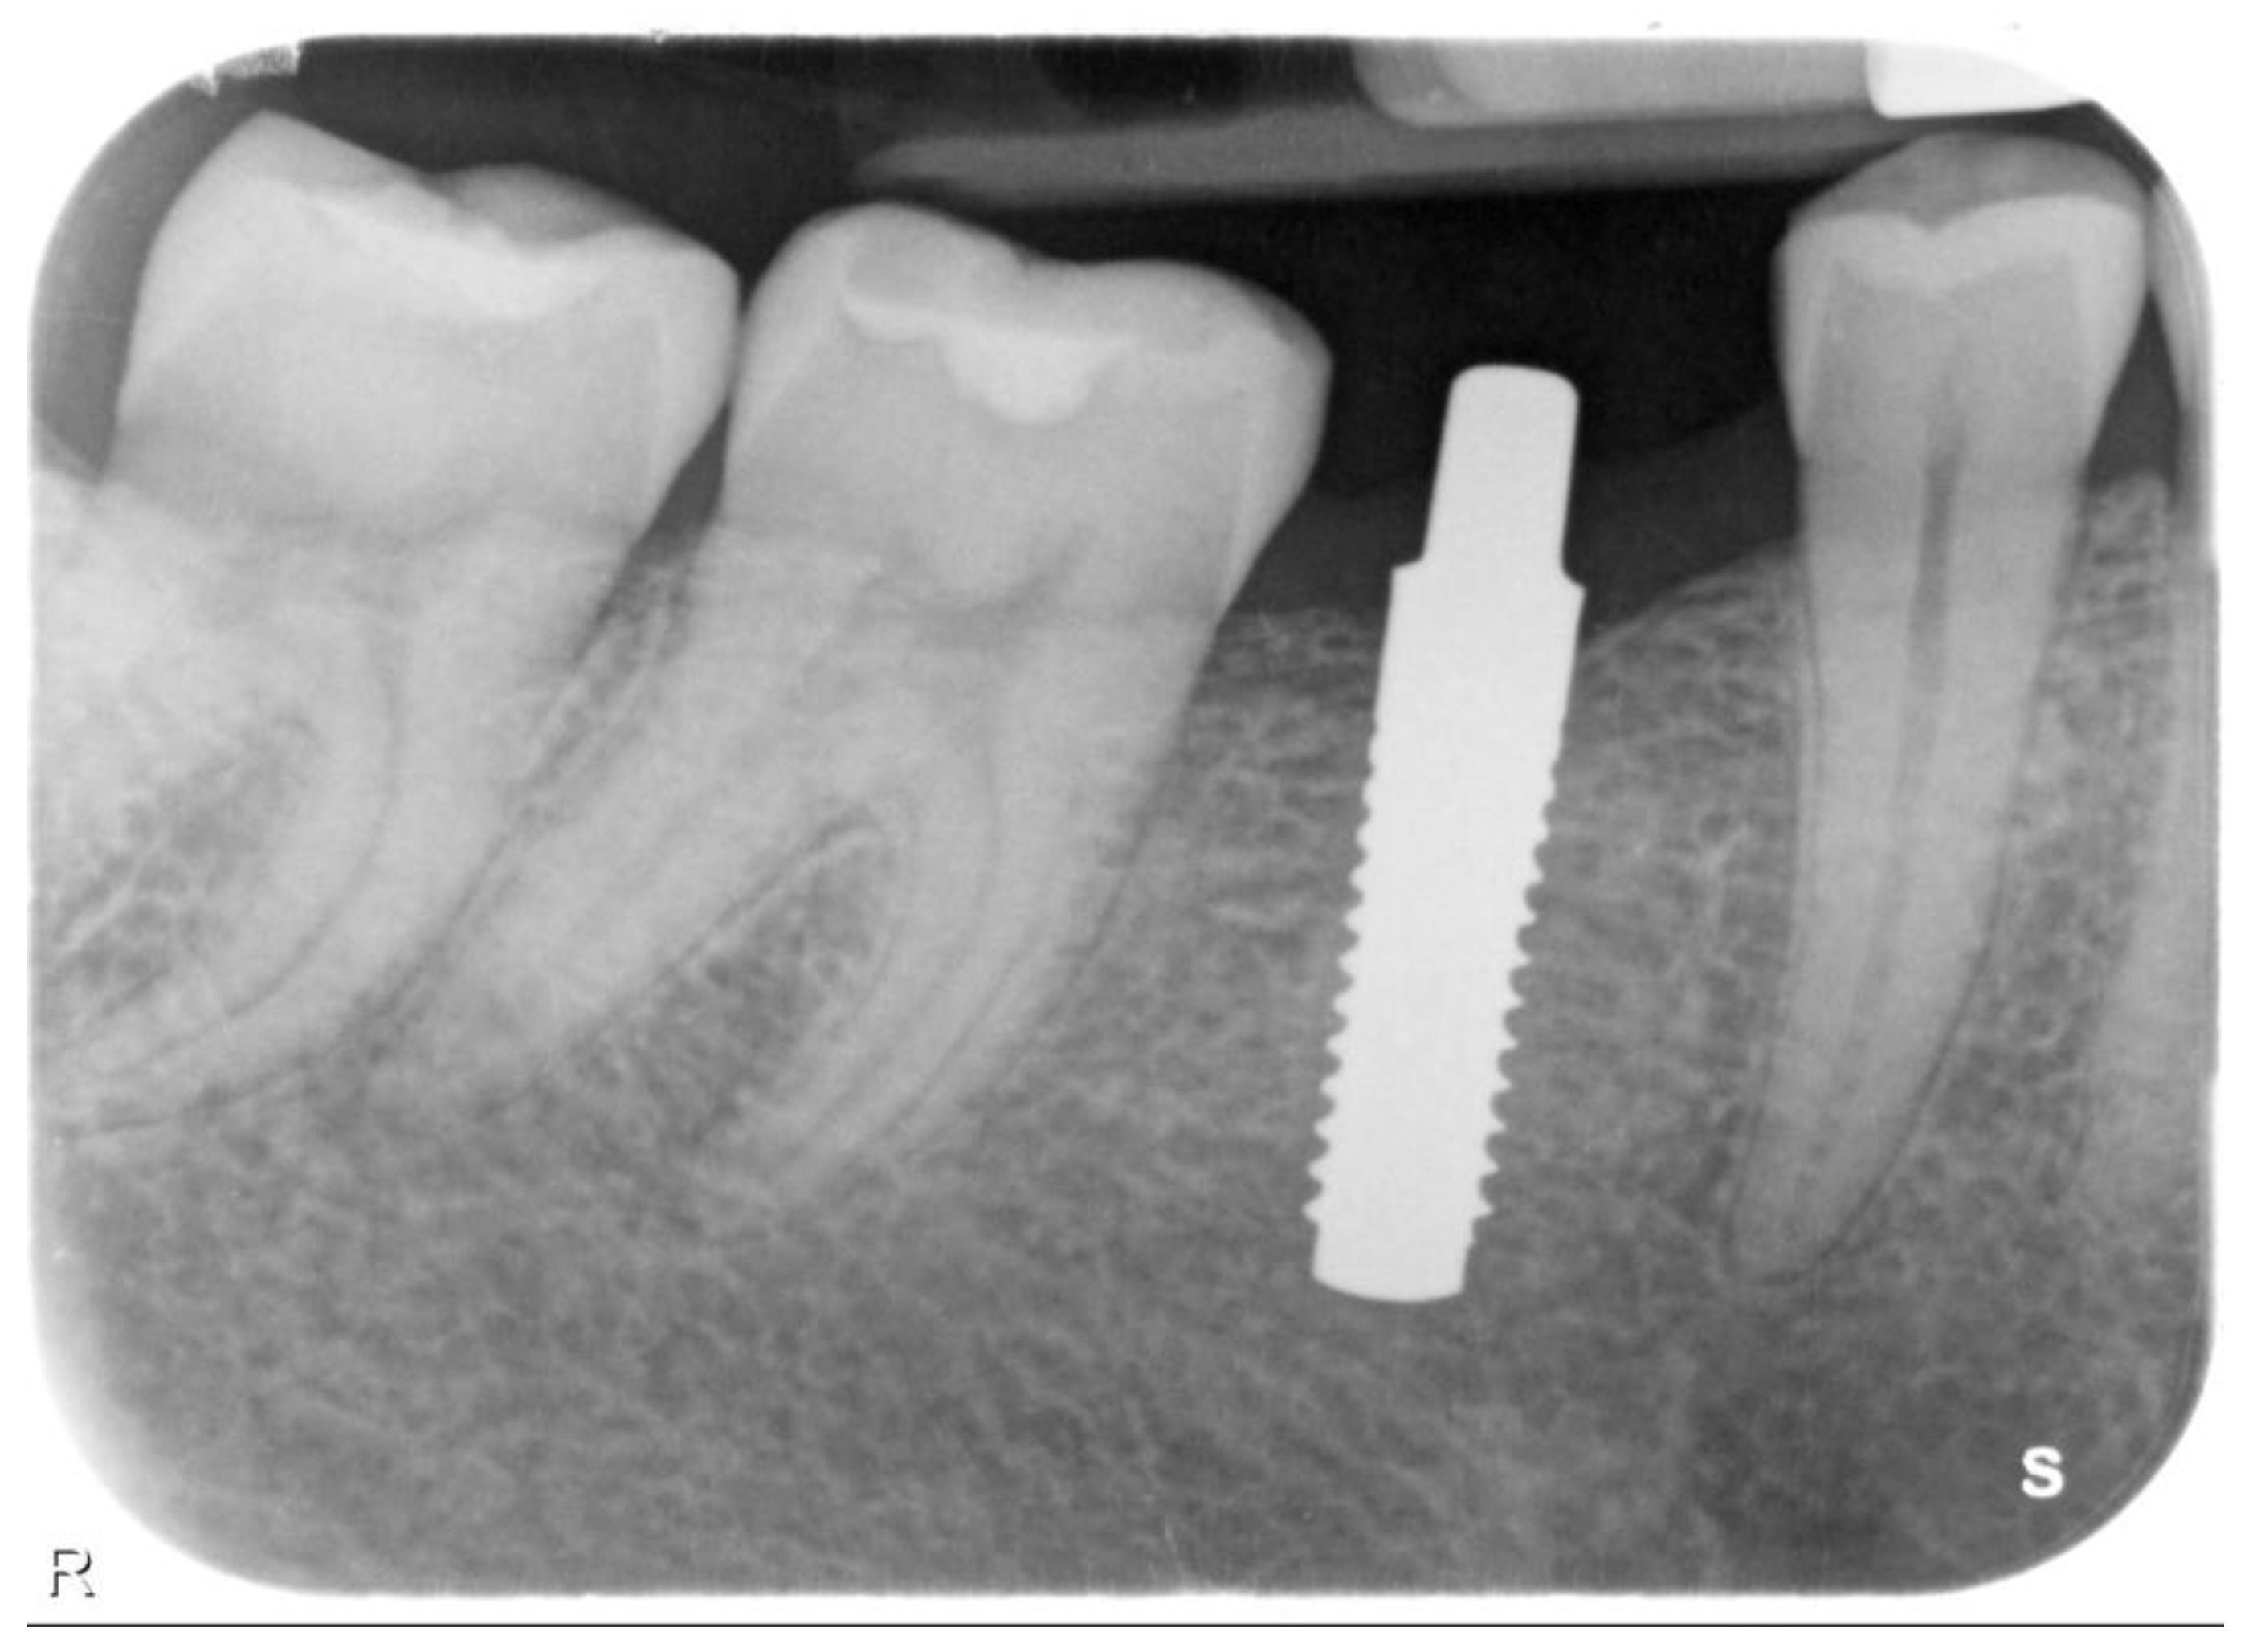

| N | Follow-Up (Months) | Age | Gender | Implant Position | Implant Diameter (mm) | Implant Length (mm) | GBR | Placement Timing (IP/DP) | Loading Timing (IL/CL) | Mean MBL (mm) (T0–T1) |

|---|---|---|---|---|---|---|---|---|---|---|

| 1 | 96 | 42 | F | 11 | 4.1 | 12 | N | IP | IL | 1.9–3.48 |

| 2 | 96 | 59 | F | 21 | 4.1 | 14 | Y | IP | IL | 1.41–1.70 |

| 3 | 94 | 41 | M | 13 | 4.1 | 12 | N | IP | IL | 2.11–3.2 |

| 4 | 92 | 50 | M | 12 | 3.3 | 12 | N | DP | IL | 2.35–3.3 |

| 5 | 83 | 35 | M | 14 | 3.3 | 12 | N | DP | IL | 1.57–1.92 |

| 6 | 88 | 37 | F | 15 | 4.1 | 12 | N | IP | IL | 2.73–2.74 |

| 7 | 73 | 43 | F | 46 | 3.3 | 12 | N | DP | CL | 1.8–1.87 |

| 8 | 73 | 46 | F | 46 | 4.1 | 12 | N | DP | CL | 1.35–1.69 |

| 9 | 62 | 37 | F | 46 | 4.1 | 10 | N | DP | CL | 1.94–2.06 |

| 10 | 59 | 47 | M | 12 | 4.1 | 12 | Y | IP | CL | 0.36–2.03 |

| 11 | 48 | 48 | M | 44 | 4.1 | 12 | N | IP | CL | 2.75–2.86 |

| 12 | 48 | 48 | M | 45 | 4.1 | 12 | N | IP | CL | 2.34–3.24 |

| 13 | 48 | 48 | M | 46 | 4.1 | 12 | N | IP | CL | 3.5–4.19 |

| 14 | 42 | 31 | M | 46 | 4.1 | 10 | N | DP | CL | 1.23–2.03 |

| 15 | 42 | 34 | M | 34 | 3.3 | 12 | N | IP | CL | 1.68–2.32 |

| 16 | 41 | 65 | F | 24 | 3.3 | 12 | Y | IP | IL | 2.1–2.82 |

| 17 | 40 | 64 | F | 21 | 3.3 | 14 | Y | IP | IL | 2.19–3.45 |

| 18 | 38 | 65 | F | 11 | 4.1 | 14 | N | IP | IL | 1.48–2.17 |

| 19 | 33 | 54 | F | 26 | 3.3 | 10 | N | IP | CL | 1.32–1.66 |

| 20 | 30 | 63 | F | 31 | 3.3 | 14 | N | IP | IL | 1.72–1.86 |

| 21 | 27 | 52 | M | 22 | 3.3 | 14 | Y | IP | CL | 1.49–2.53 |

| 22 | 27 | 69 | F | 36 | 4.1 | 12 | Y | DP | CL | 1.72–3.57 |